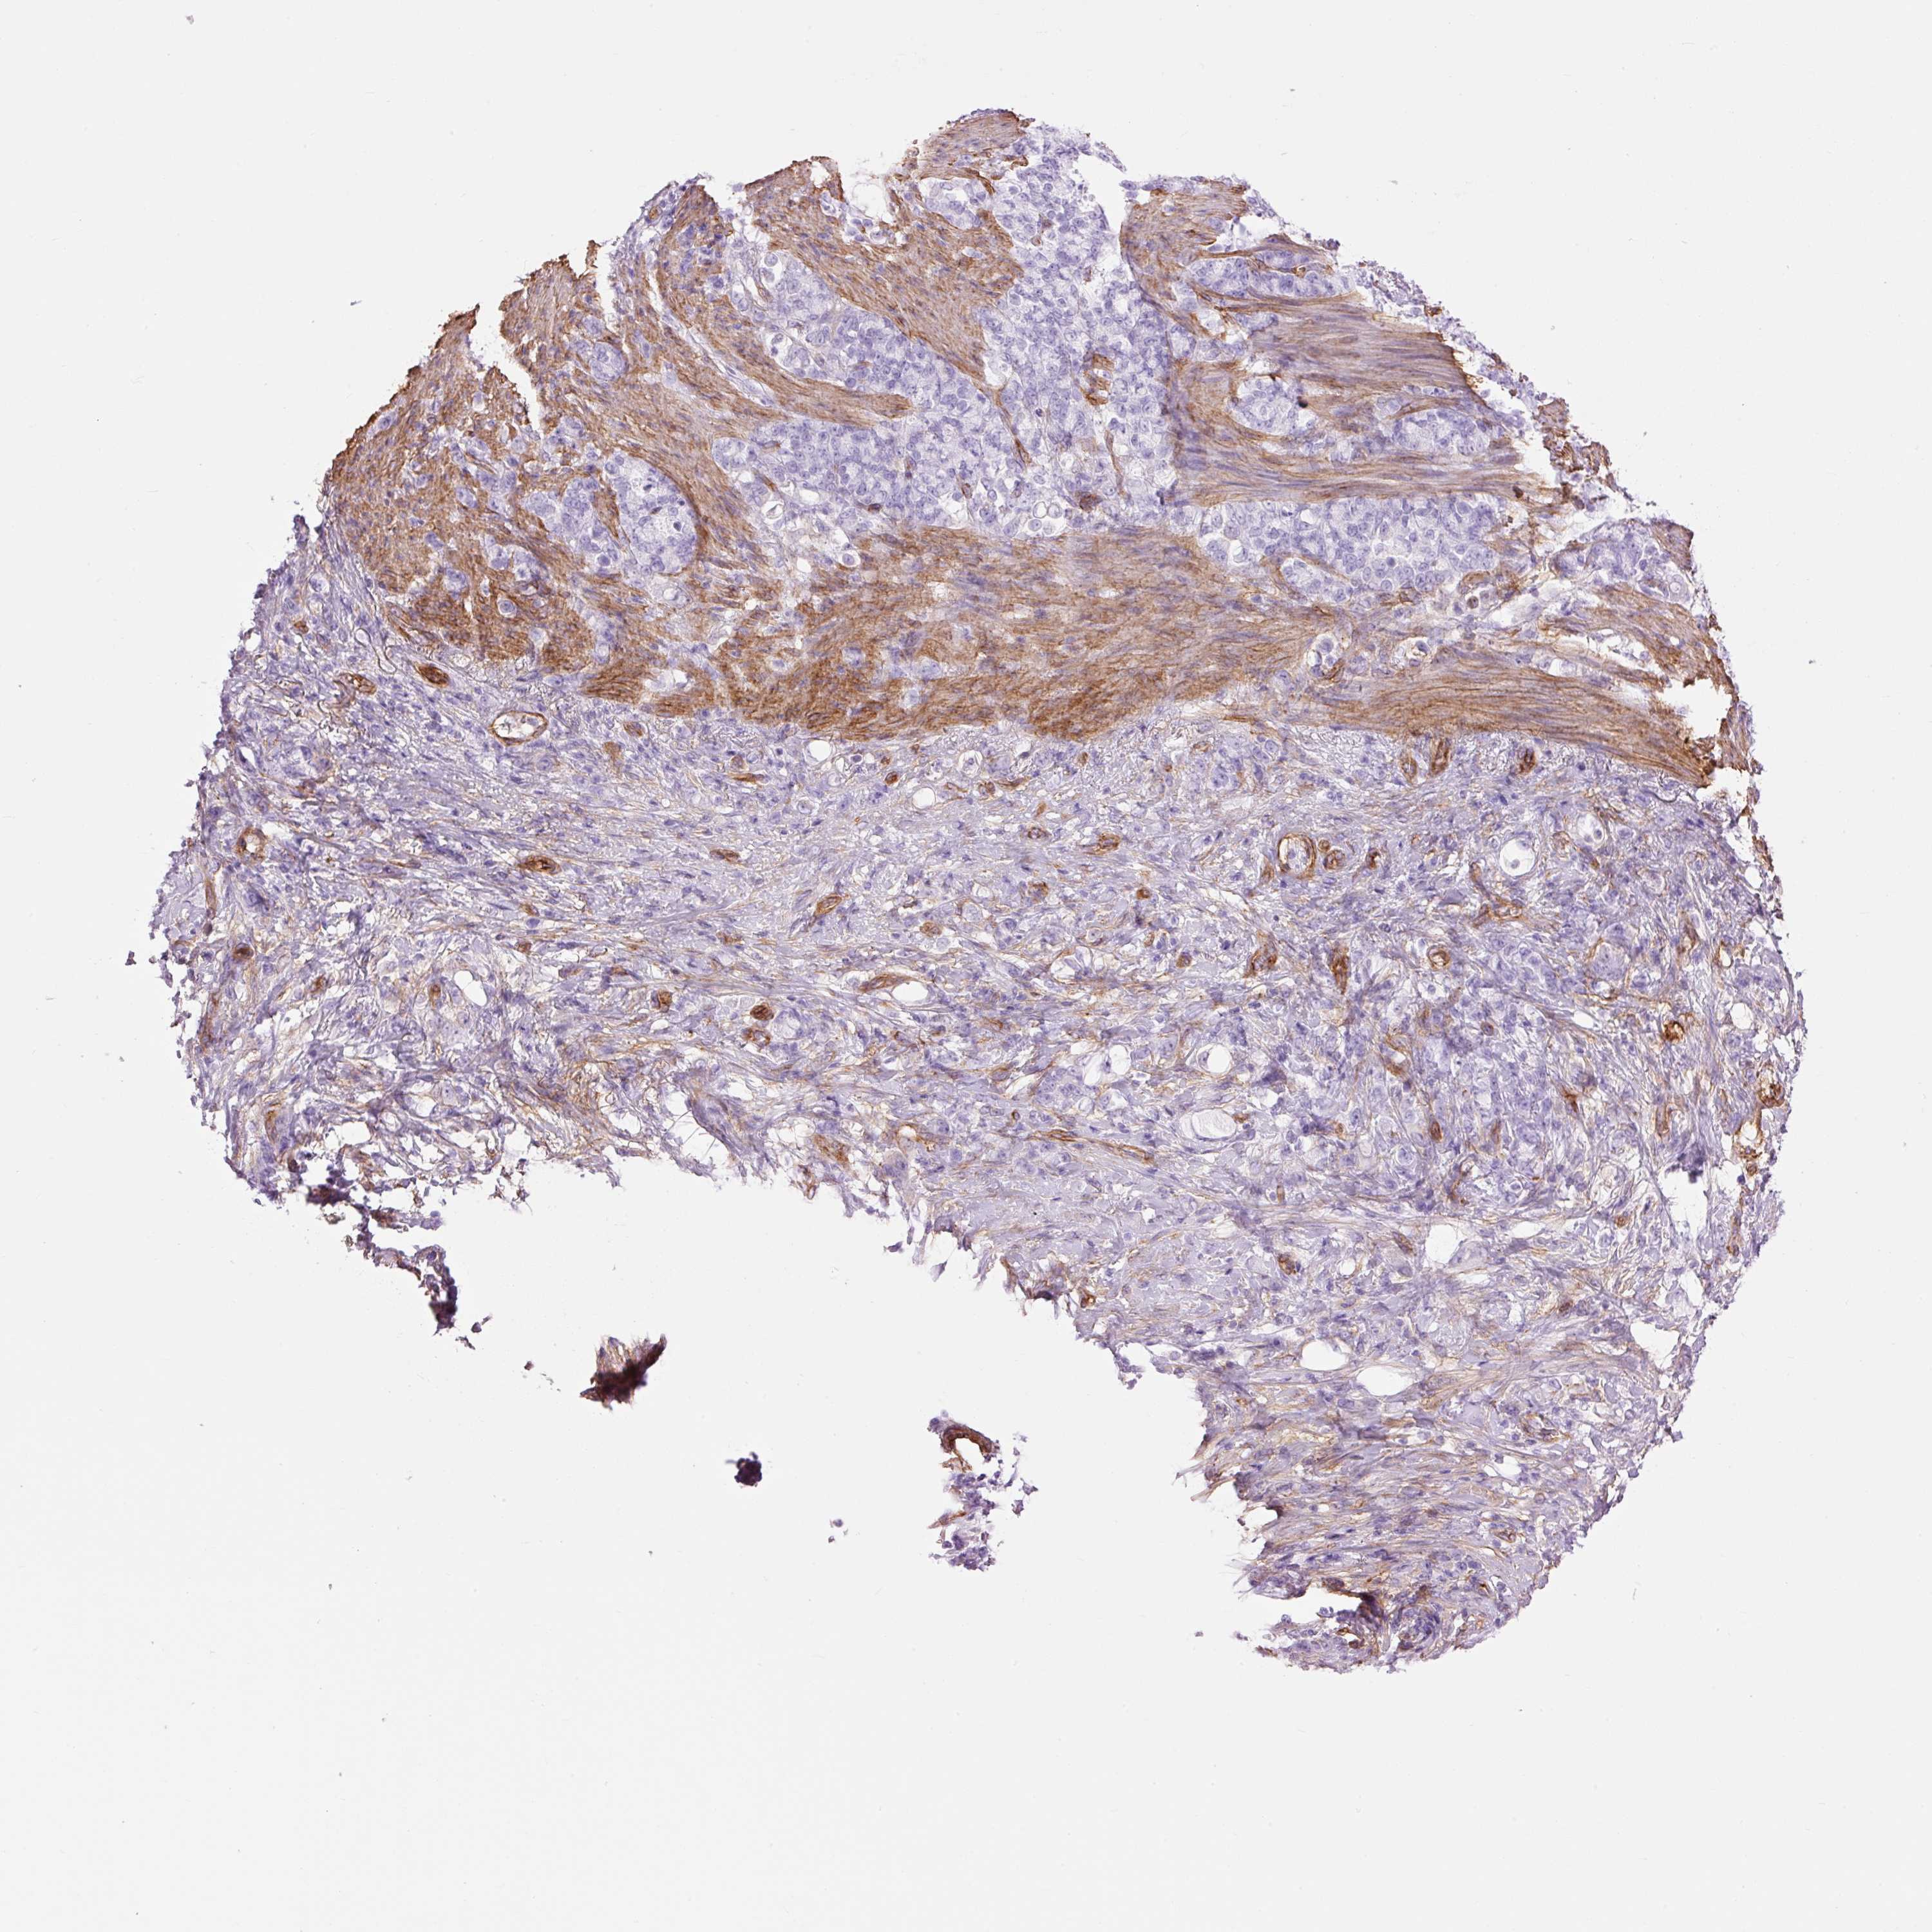

STOMACH CANCER - Protein expressioni

A mouse-over function shows sample information and annotation data. Click on an image to view it in a full screen mode. Samples can be filtered based on level of antibody staining by selecting one or several of the following categories: high, medium, low and not detected. The assay and annotation is described here.

Note that samples used for immunohistochemistry by the Human Protein Atlas do not correspond to samples in the TCGA dataset.

Antibody stainingi

Antibody staining in the annotated cell types in the current human tissue is reported as not detected, low, medium, or high, based on conventional immunohistochemistry profiling in selected tissues. This score is based on the combination of the staining intensity and fraction of stained cells.

Each image is clickable and will lead to virtual microscopy that enables deeper exploration of all samples and also displays staining intensity scores, fraction scores and subcellular localization as well as patient and tissue information for each sample.

Antibody HPA049326

Antibody CAB003791

Staining

High

Medium

Low

Not detected

Intensity

Strong

Moderate

Weak

Negative

Quantity

>75%

75%-25%

<25%

None

Location

Nuclear

Cytoplasmic/membranous

Cytoplasmic/membranous,nuclear

Adenocarcinoma, NOS

Adenocarcinoma, High grade